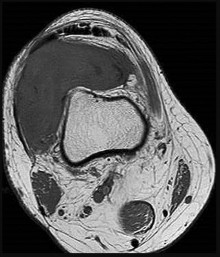

Question 15

Following a traumatic knee injury, a 24-year-old athlete undergoes an arthroscopic meniscal repair. Which zone of the meniscus has the highest healing potential, and from which vessels does it derive its primary blood supply?

Explanation

The peripheral 10% to 30% of the meniscus (the red-red zone) is well-vascularized and thus has the highest healing potential. The blood supply to this peripheral zone is derived from the capsular and synovial branches of the medial and lateral, superior and inferior geniculate arteries. The central white-white zone is avascular and relies on diffusion from synovial fluid, lacking the intrinsic capacity to heal.